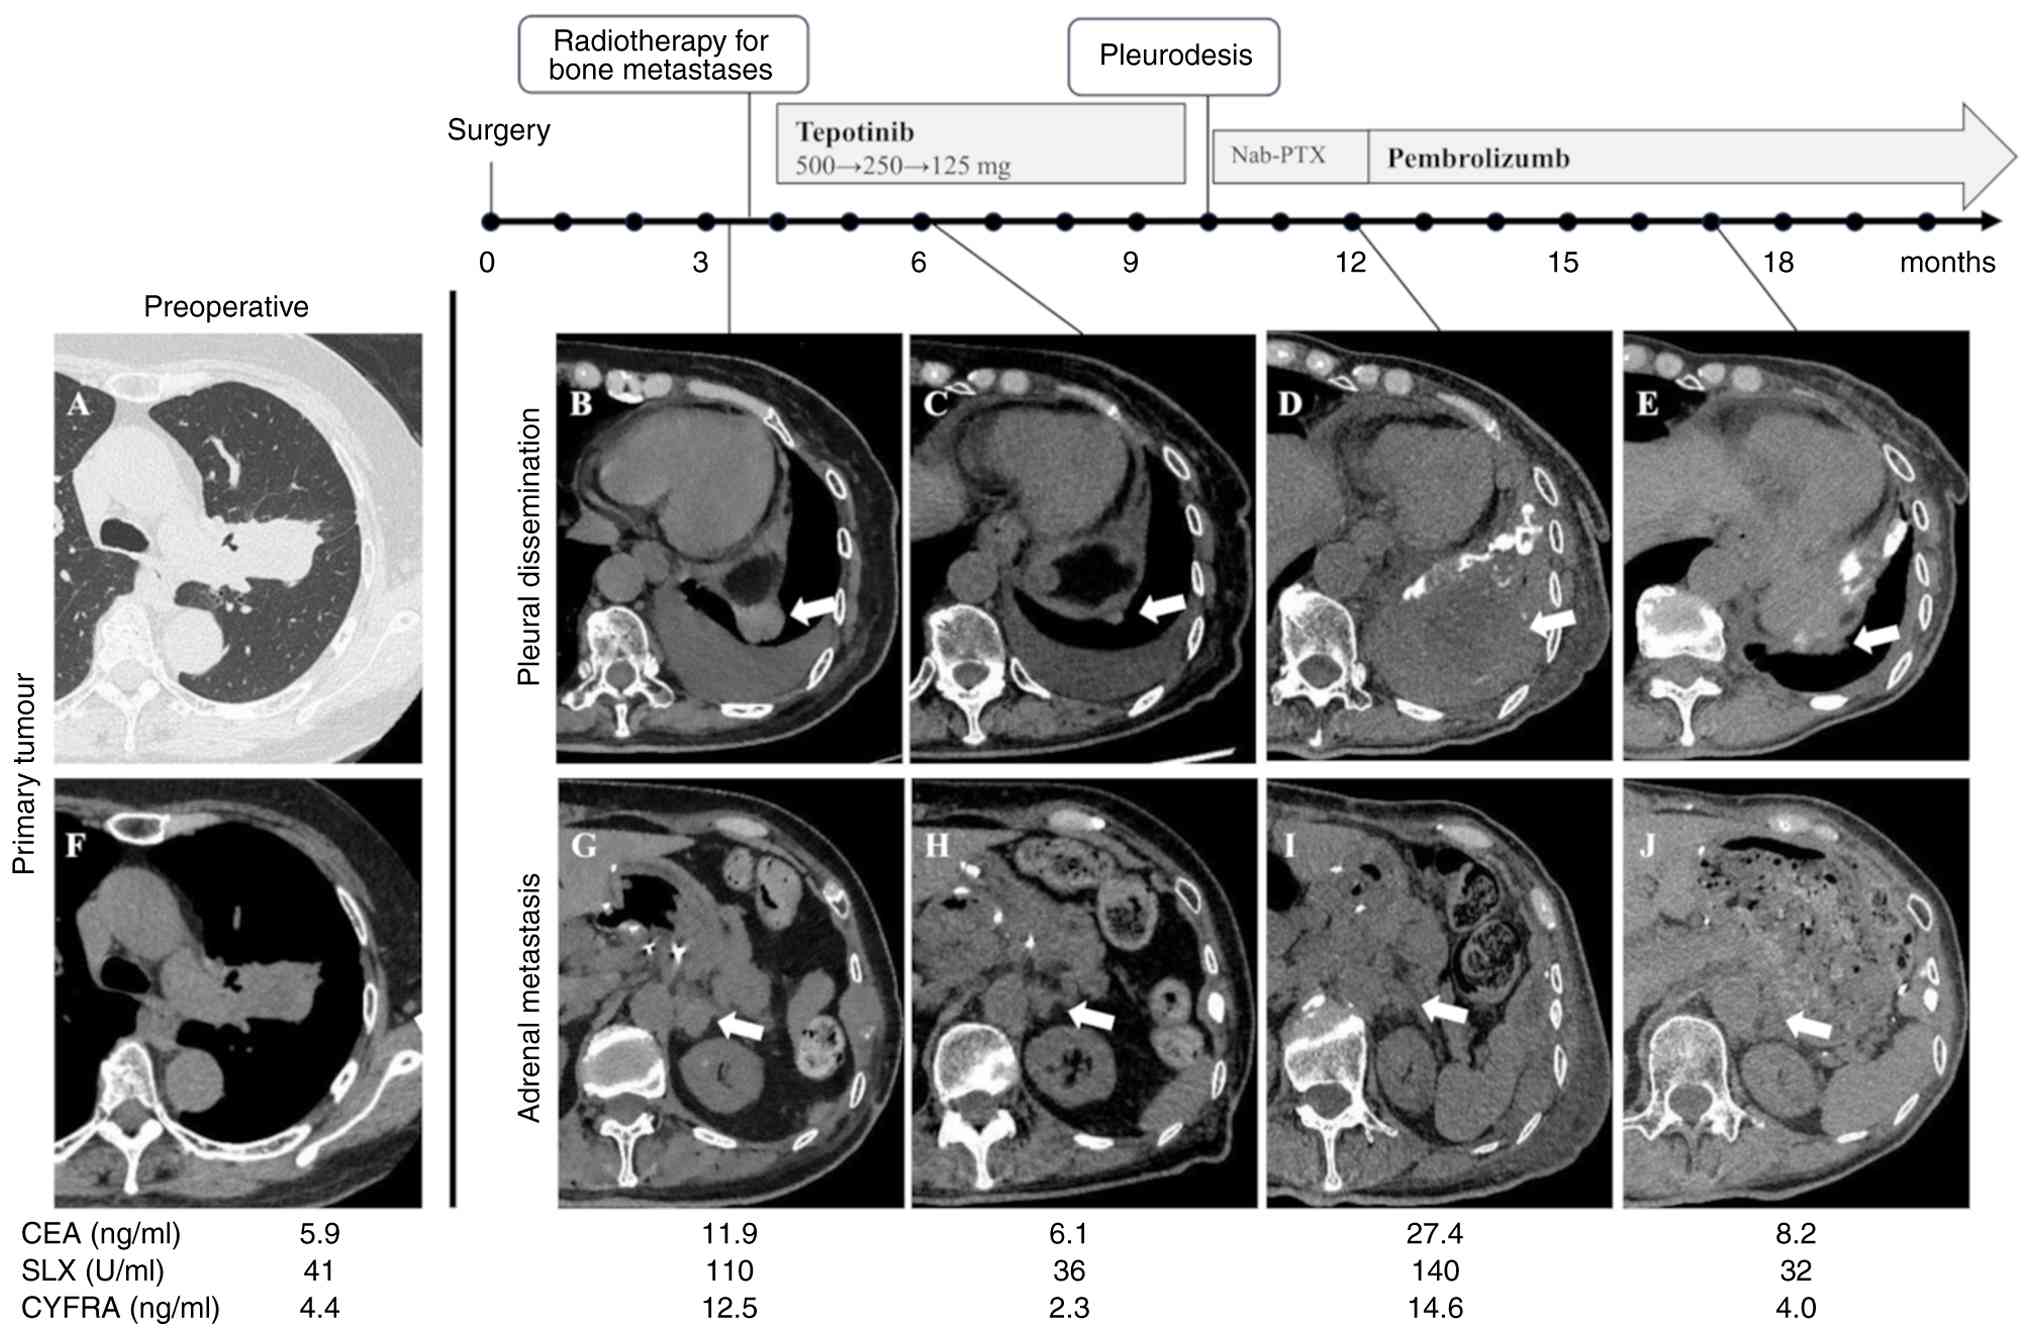

A 75-year-old woman with no history of smoking underwent left upper lobectomy, pulmonary angioplasty, and lymph node dissection (ND2a-2) for an approximately 4-cm mass in the left upper lobe with pulmonary artery invasion (Fig. 1A and F) in May 2022 at Niigata University Medical and Dental Hospital (Niigata, Japan). The patient had comorbidities such as hypertension, chronic kidney disease, and atrial fibrillation.

Computed tomography images over the

clinical course. (A) Primary tumour of the left upper lobe shown on

lung window. (B) Pleural dissemination of the left diaphragm at the

time of postoperative recurrence, 26 mm in diameter. (C) Pleural

dissemination of the left diaphragm decreased to 5 mm in diameter 2

months after tepotinib initiation. (D) Pleural dissemination of the

left diaphragm had grown to 93 mm in diameter prior to the

initiation of pembrolizumab. (E) Pleural dissemination of the left

diaphragm decreased to 25 mm in diameter 5 months after initiation

of pembrolizumab. (F) Primary tumour of the left upper lobe shown

on mediastinal window. (G) Left adrenal metastasis at the time of

postoperative recurrence, 21 mm in diameter. (H) Left adrenal

metastasis decreased to 12 mm in diameter 2 months after initiation

of tepotinib. (I) Size of left adrenal metastasis remained largely

unchanged, measuring 13 mm before initiation of pembrolizumab. (J)

Size of left adrenal metastasis remained unchanged, measuring 13 mm

5 months after initiation of pembrolizumab. Nab-PTX, nanoparticle

albumin-bound paclitaxel; CEA, carcinoembryonic antigen; SLX,

Sialyl Lewis X antigen; CYFRA, cytokeratin 19 fragment.

Figure 1.

Computed tomography images over the clinical course. (A) Primary tumour of the left upper lobe shown on lung window. (B) Pleural dissemination of the left diaphragm at the time of postoperative recurrence, 26 mm in diameter. (C) Pleural dissemination of the left diaphragm decreased to 5 mm in diameter 2 months after tepotinib initiation. (D) Pleural dissemination of the left diaphragm had grown to 93 mm in diameter prior to the initiation of pembrolizumab. (E) Pleural dissemination of the left diaphragm decreased to 25 mm in diameter 5 months after initiation of pembrolizumab. (F) Primary tumour of the left upper lobe shown on mediastinal window. (G) Left adrenal metastasis at the time of postoperative recurrence, 21 mm in diameter. (H) Left adrenal metastasis decreased to 12 mm in diameter 2 months after initiation of tepotinib. (I) Size of left adrenal metastasis remained largely unchanged, measuring 13 mm before initiation of pembrolizumab. (J) Size of left adrenal metastasis remained unchanged, measuring 13 mm 5 months after initiation of pembrolizumab. Nab-PTX, nanoparticle albumin-bound paclitaxel; CEA, carcinoembryonic antigen; SLX, Sialyl Lewis X antigen; CYFRA, cytokeratin 19 fragment.

Three months postoperatively, the patient experienced left shoulder pain, and visited the hospital, with an Eastern Cooperative Oncology Group performance status of 2 owing to the pain and state of recovery postoperatively. Computed tomography (CT) showed a 26-mm nodule on the left diaphragm, which was considered to indicate pleural dissemination, bilateral adrenal metastases (right: 11 mm, left: 21 mm), and multiple bone metastases, including to the fourth cervical vertebra and left ribs (Fig. 1B and G). The CEA level was 11.9 ng/ml (normal range, ≤5.0 ng/ml), SLX level was 110 U/ml (normal range, ≤38 U/ml), and CYFRA level was 12.5 ng/ml (normal range, ≤3.5 ng/ml). Palliative radiotherapy was administered for bone metastases, with 30 Gy in 10 fractions to the fourth cervical vertebra and 20 Gy in 5 fractions to the left eighth rib.

Two months after initiating tepotinib, CT imaging showed a reduction in pleural dissemination on the left diaphragm (5 mm) and in bilateral adrenal metastases (right: 5 mm, left: 12 mm) (Fig. 1C and H), and the response was assessed as a partial response (PR).

However, 5 months after the initiation of tepotinib, a CT scan showed that although the reduction in the extent of the bilateral adrenal metastases was maintained, the pleural dissemination had progressed and the amount of left pleural effusion had increased (pleural dissemination: 93 mm, left adrenal metastasis: 13 mm, Fig. 1D and I), leading to the diagnosis of progressive disease (PD).

Consequently, the patient underwent pleural drainage and pleurodesis using talc. At the beginning of the secondary treatment, the patient was found to have inflammation in the left lower lobe, which was possibly caused by pleurodesis. Owing to concerns regarding the progression of pulmonary inflammation, ICIs were avoided. Therefore, nab-paclitaxel was administered as the second-line therapy. After the first course of nab-paclitaxel, the size of the pleural dissemination increased, accompanied by an increase in chest pain, leading to the assessment of PD. At that time, the ground-glass opacity of the left lower lobe had disappeared; therefore, pembrolizumab was started as third-line therapy. Thereafter, the left pleural dissemination shrunk and the chest pain disappeared; the response was assessed as PR (pleural dissemination: 25 mm, left adrenal metastasis: 13 mm, Fig. 1E and J). The patient had no apparent adverse events. Nine months after the initiation of pembrolizumab, the patient required palliative radiotherapy for enlargement of a left iliac metastasis. No significant disease progression was observed at other sites, and pembrolizumab treatment was successfully continued for a total of 19 months. Subsequently, the patient developed infection and heart failure. Owing to a decline in performance status, anticancer therapy was discontinued, and the patient died of primary disease 36 months after surgery at the receiving hospital.